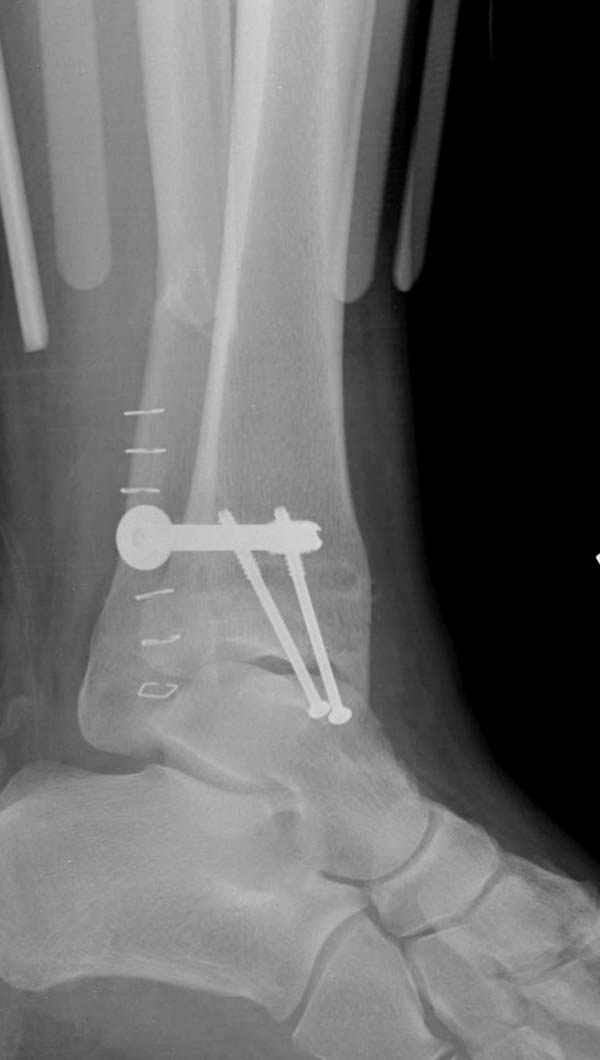

Недавний случай, больной 56 лет получил политравму в Англии, после переведен в США, где его успешно лечил местный ортопед, огромная статья в газете об успешной операции, своеобразный пиар, из-за того, что больной был американский пожарник на пенсии, и за его переезд было заплачено международным пожарным союзом, короче по другим показаниям перевели больного в наш университетский госпиталь.

После 5-6 недели после травмы сделана повторная операция, обошлись без удлинения малоберцовой.